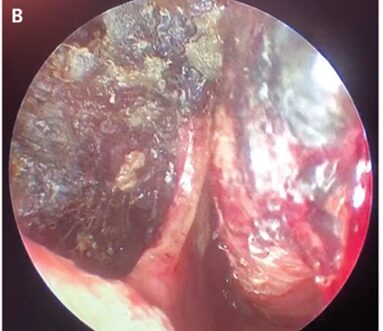

鼻内視鏡検査では、鼻腔内に壊死のような黒色痂皮と鼻中隔穿孔を認めた。